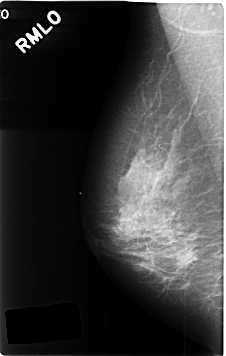

C_0466_1.RIGHT_MLO

RIGHT_MLO LINES 4624 PIXELS_PER_LINE 2928 BITS_PER_PIXEL 12 RESOLUTION 50 NON_OVERLAY